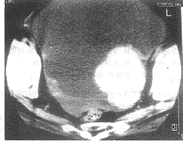

图1 浆液性乳头状囊腺癌 CT扫描示盆腹腔内巨大不规则形囊实性肿块,大小为15cm×11cm×10cm,囊性部分CT值为10~22Hu,实性部分CT值为35~45Hu,壁结节CT值为34.8Hu 图2 低分化浆液性囊腺瘤 CT平扫示右侧卵巢不规则形囊实性肿

块,囊壁厚薄不均,CT值为35~45Hu,囊性部分CT值为10~22Hu